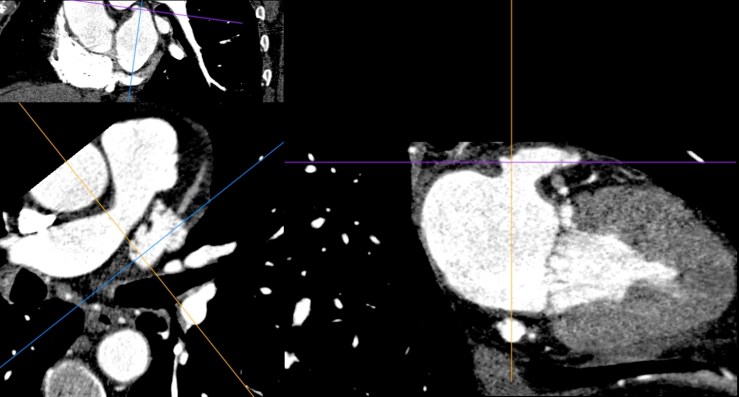

Όταν, λοιπόν, αποφασίζουμε να προχωρήσουμε, το αποτέλεσμα πρέπει να είναι κάπως έτσι:

Και στις MPR τομές, να μη φαίνεται σκιαγράφηση του σώματος του ωτίου — ακόμα και ένα μικρό peri-device leak (PDL) θα τo «ασπρίσει» –, ούτε βέβαια θρόμβος (device-related thrombosis, DRT).